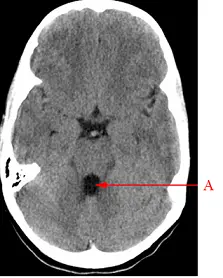

腦部電腦斷層掃描影像中,箭號 A 所指的解剖構造為何?

- 影像為一張腦部無對比劑的軸狀電腦斷層掃描(Axial non-contrast head CT)。

- 切面高度判斷:影像兩側可見高密度(亮白)的顳骨岩部(petrous bone)及含空氣的乳突氣室(mastoid air cells),顯示此切面位於後顱窩(posterior fossa)的高度。

- 腦幹與小腦:中央前方較為膨大圓潤的軟組織結構為橋腦(pons);在橋腦後方的廣大腦組織則為小腦(cerebellum)。

- 箭號 A 結構:箭號 A 指向一個位於中線的腔室結構,該空間呈現低密度(呈現暗色,代表內部充滿腦脊髓液 CSF),位於橋腦後方、小腦前方。

- (A) 基底動脈(basilar artery):基底動脈位於橋腦前方的橋腦前池(prepontine cistern)中。在 CT 影像上,通常呈現為腦幹前方中線處的一個小圓點(若無顯影劑,可能呈現等密度或輕微高密度)。與箭號 A 指向腦幹後方的位置不符。

- **(B) 第四腦室(fourth ventricle